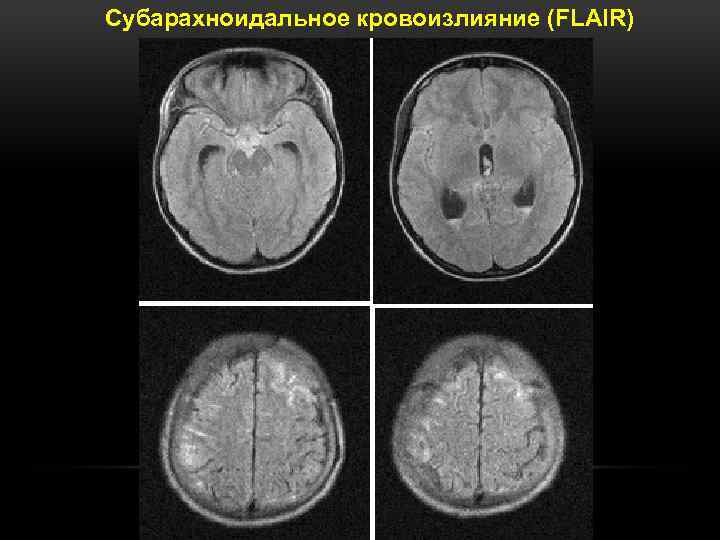

Субарахноидальное кровоизлияние (FLAIR)